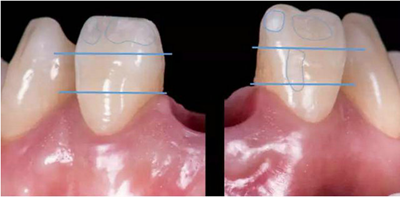

1、中切牙長(zhǎng)度10~11mm,寬長(zhǎng)比75%~80%,比側(cè)切牙寬2~3mm,比尖牙寬1~1.5mm。

2、中切牙可以與尖牙頸緣同高,理想的側(cè)切牙齦緣位置應(yīng)低于中切牙0.5~2mm。

技師獲得模型后,行DSD設(shè)計(jì),根據(jù)患者口內(nèi)情況、咬合關(guān)系及患者意愿進(jìn)行牙齒形態(tài)調(diào)整。根據(jù)DSD設(shè)計(jì)進(jìn)行診斷蠟型制作。制作過程中需充分考慮影響美學(xué)重建修復(fù)的因素,包括中切牙寬長(zhǎng)比、牙齒形態(tài)、牙齦曲線、切緣弧度(咬合關(guān)系)等。

制作診斷蠟型:

可以觀察到鄰牙形態(tài)為尖圓形,為了獲得一個(gè)美觀效果且能關(guān)閉黑三角,牙齒形態(tài)由鄰牙的尖圓形改為方圓形。